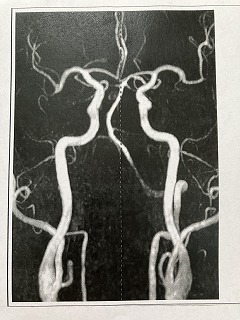

090 脳ドック

2024.18.14 荒尾市民病院 2023.08.10 荒尾市民病院

2024 PDF 2023 PDF

22.9.16 荒尾市民病院

2014(H26)7.29 岡山淳風会